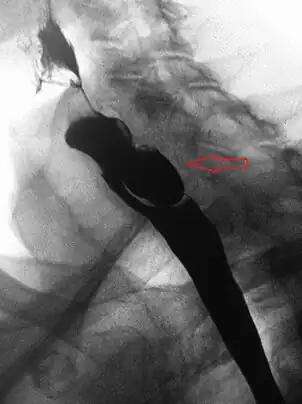

Lateral X-ray of a Zenker's diverticulum